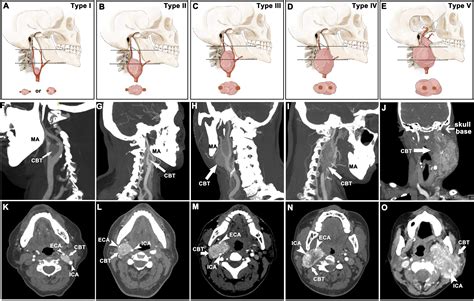

The carotid body is a small, oval-shaped gland situated deep within the neck where the common carotid artery splits into the internal and external carotid arteries. A Carotid Body Tumor arises from the chief cells, also known as glomus cells, which are part of the paraganglion system. Because this area is rich in blood supply and highly vascular, these tumors are known for being exceptionally blood-rich, which historically made surgical intervention challenging.

Diagnosing a Carotid Body Tumor requires a combination of physical examination and advanced imaging studies. When a physician suspects such a growth, they typically use specific diagnostic tools to differentiate it from enlarged lymph nodes or other neck masses. The “Lyre sign,” seen on imaging, is a classic finding where the internal and external carotid arteries are splayed apart by the tumor mass.